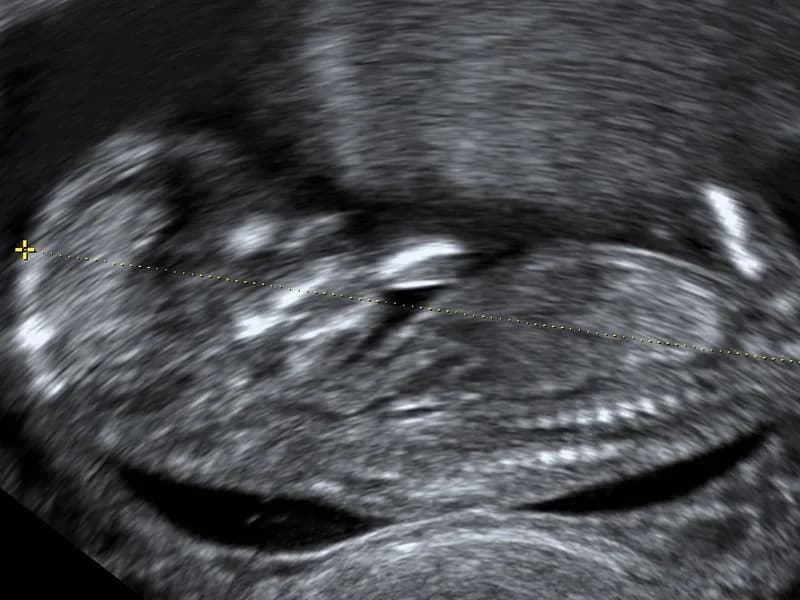

- –Praćenje trudnoće(Pregled trudnice Rana prenatalna dijagnostika UZV - Anomaly scan 3D/4D anatomija i fetalno ponašanje)

- –UZV u ranoj trudnoći

- –Ultrazvučni pregled u 2. i 3. tromjesječju

- –Pregled trudnice(Pregled trudnice se sastoji od: kontrole urina na biokemijskoj traci s dijagnostikom 10 parametara, mjerenja krvnog tlaka, tjelesne težine, analize nalaza krvnih pretraga i dogovora za slijedeće pretrage, konzultacija o prehrani i tjelovježbi /mirovanju, te ovisno o tjednima trudnoće, vaginalnog pregleda stanja vrata maternice i ultrazvuka. U prvom tromjesječju ultrazvuk se radi vaginalno, a kasnije preko trbušne stjenke.)